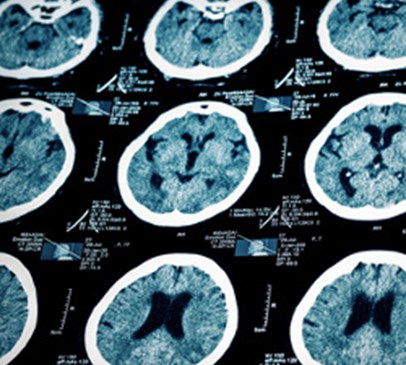

New treatment for wide-necked brain aneurysm Main Image

New treatment for wide-necked brain aneurysm

Neurosurgeons at Jefferson Hospital for Neuroscience in Philadelphia are pioneering a new treatment for wide-necked brain aneurysms, which could eventually replace current methods. The liquid embolic (blocking) system, which has been FDA approved for limited trial in the USA, is a potentially exciting breakthrough in aneurysm treatment.

An aneurysm is a weakness in a vessel or artery that causes part of the arterial wall to balloon out. This puts an individual at risk of haemorrhage if the aneurysm bursts. Erol Veznedaroglu at Jefferson is one of the few surgeons selected to trial the use of the liquid embolic system to fill wide-necked aneurysms, which have a wide opening where the aneurysm arises.

Wide-necked aneurysms are relatively uncommon and have previously proved difficult to treat by the traditional method of inserting a coil. This is because the wide opening means the coil can slip out of the aneurysm sac. The new treatment uses a liquid, inserted via a catheter, which solidifies inside the aneurysm and cuts off its blood supply, thus preventing it from increasing in size and rupturing.